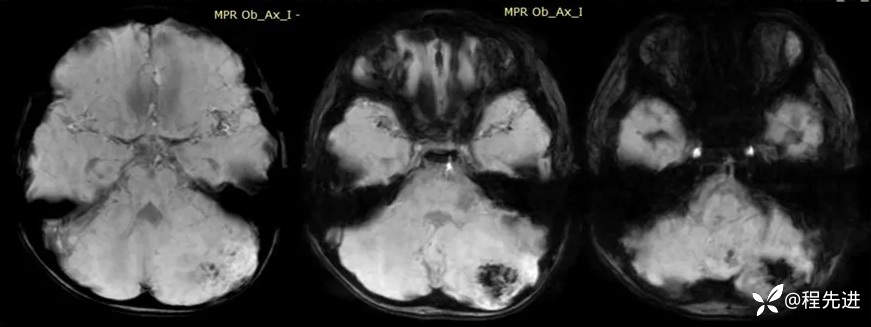

【患者信息】:男,6岁

【主诉】:查体发现左侧小脑半球占位3个月

【现病史及既往史】:患者3个月前因鼻塞至外院就诊,行头颅CT检查偶然发现颅内占位

【检查】